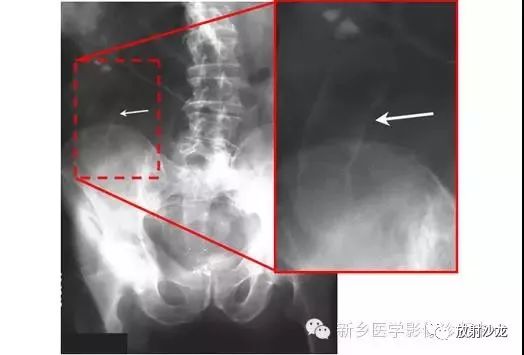

上图腹部平片检查是一6岁男孩,出现呕吐和急性右髂窝疼痛进行的。两个关键的发现在哪里?(提示:通过放射科医生所提供的箭头可以缩小关注点。)

右髂窝多个扩张的小肠襻出现小的钙化结节。小肠袢可与大肠区分开来,因为小肠的环状襞延伸至整个肠壁,而结肠袋只是部分延伸存在。在右下腹(箭头)的钙化结节高度提示阑尾粘连。这个病人开腹手术发现阑尾粘连致小肠梗阻。